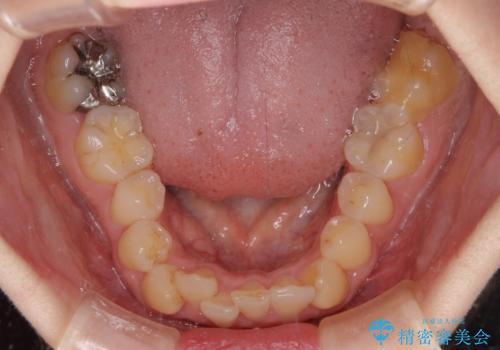

- 前歯のデコボコで前方に出ていることを気にして来院された患者様です。

上顎前歯が捻れて前方に飛び出しており、下顎前歯もそれに沿うようにデコボコとなっていました。

IPR(歯と歯の間を削る処置)によりスペースを獲得して上下顎前歯のデコボコを改善し、飛び出している前歯が引っ込むように設定し、インビザラインにて矯正治療を行うこととしました。